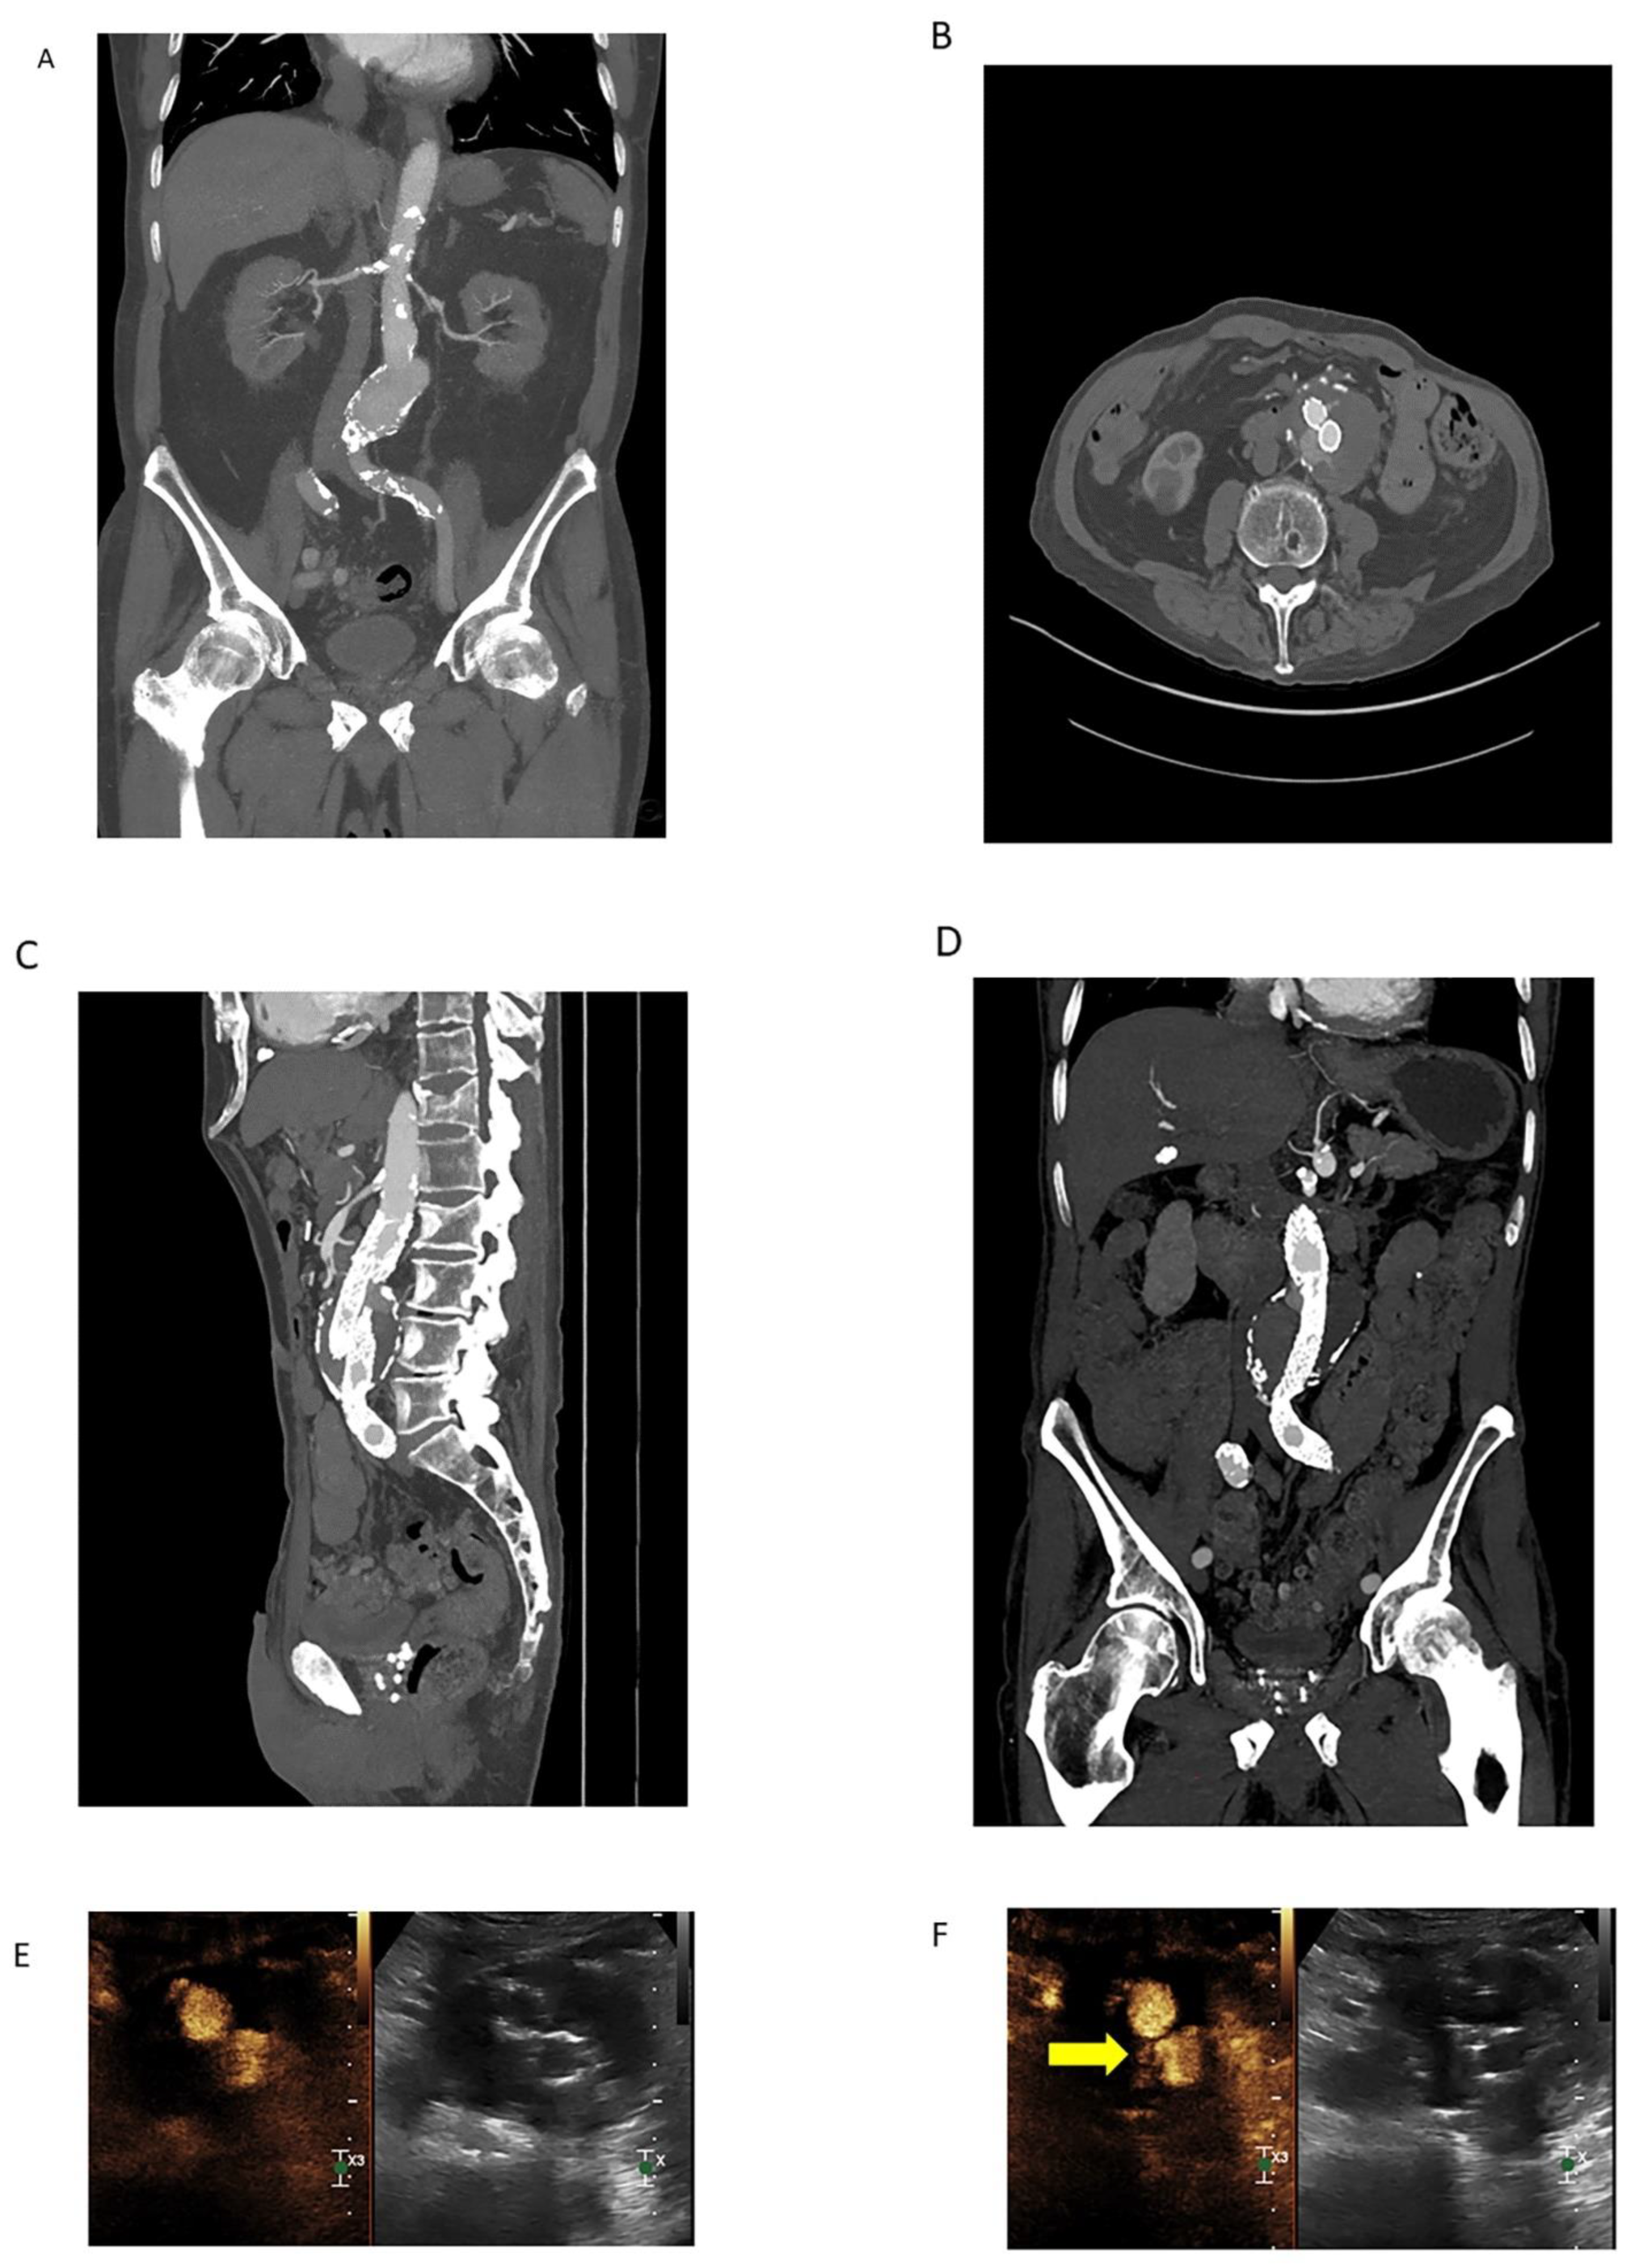

3.2.3. Contrast-Enhanced Ultrasound